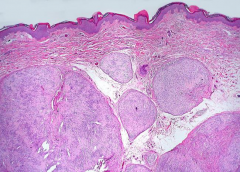

• 听神经鞘瘤大小分级和临床分期

听神经鞘瘤大小分级和临床分期

2021-09-06 10:24:28

什么是听神经鞘瘤?听神经鞘瘤是桥小脑角区较多发的肿瘤, 约占该区肿瘤的80%。听神经鞘瘤(Acoustic neurinoma)占颅内肿瘤的7.79%~10.64%,占颅内神经鞘瘤...